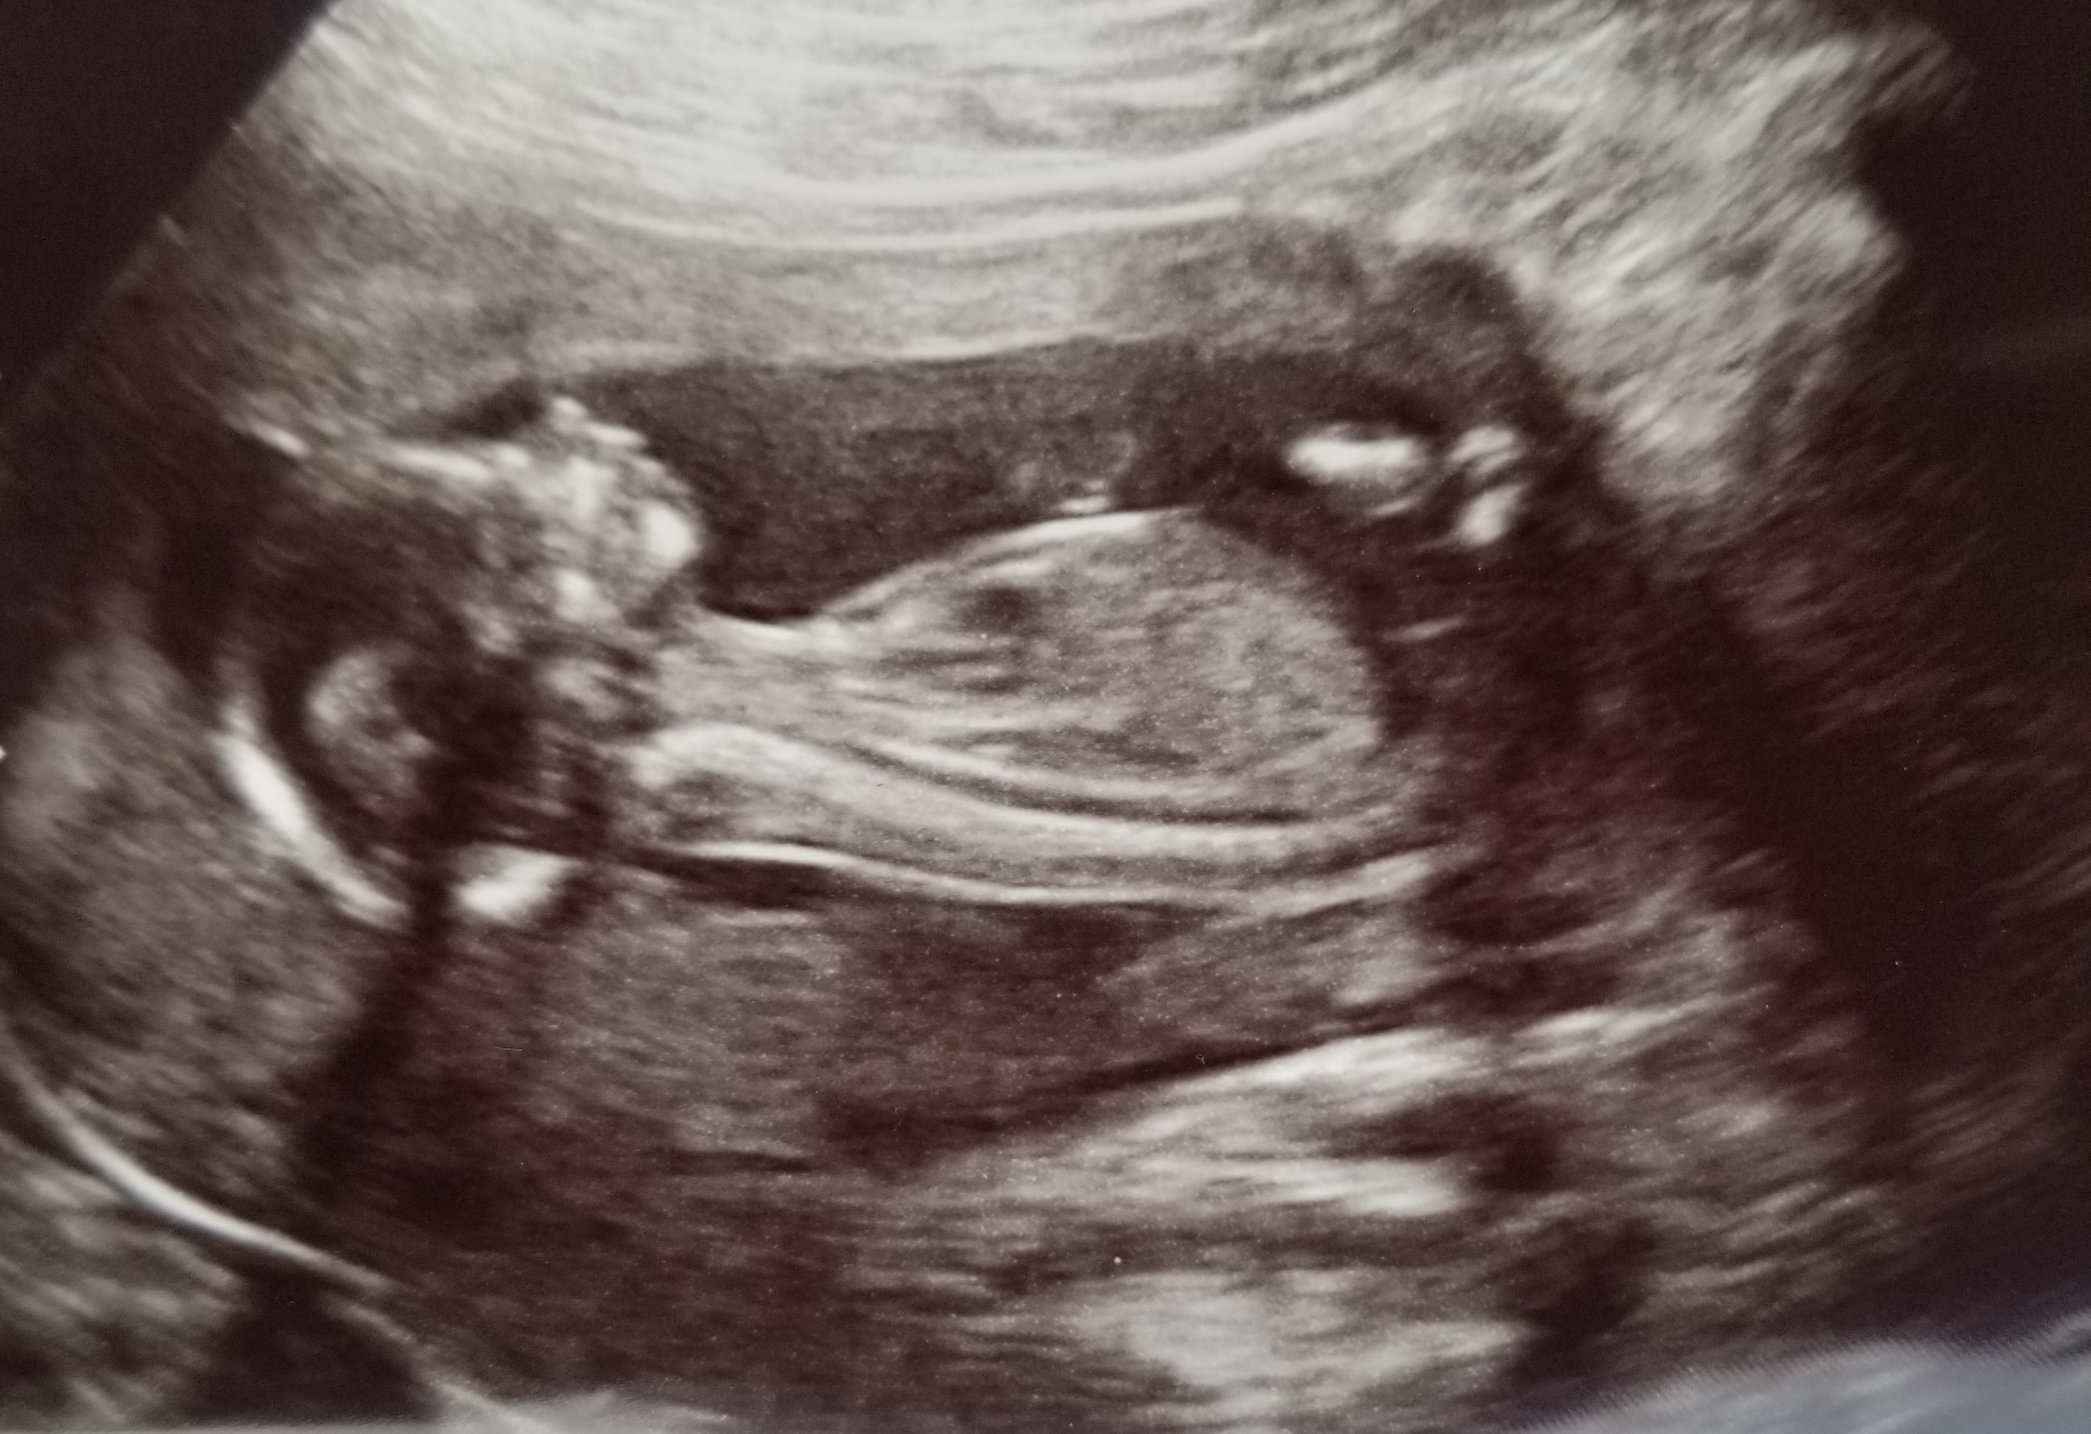

Baby #3. I had my anatomy scan on Jan 2 with the maternal fetal medicine doctor. He's currently breech and facing my spine. The scan took a while, but all looked good enough to cancel my consultation with the doctor afterward. Due to age, and other risk factors, I go back in for another ultrasound in 4 weeks to check growth.